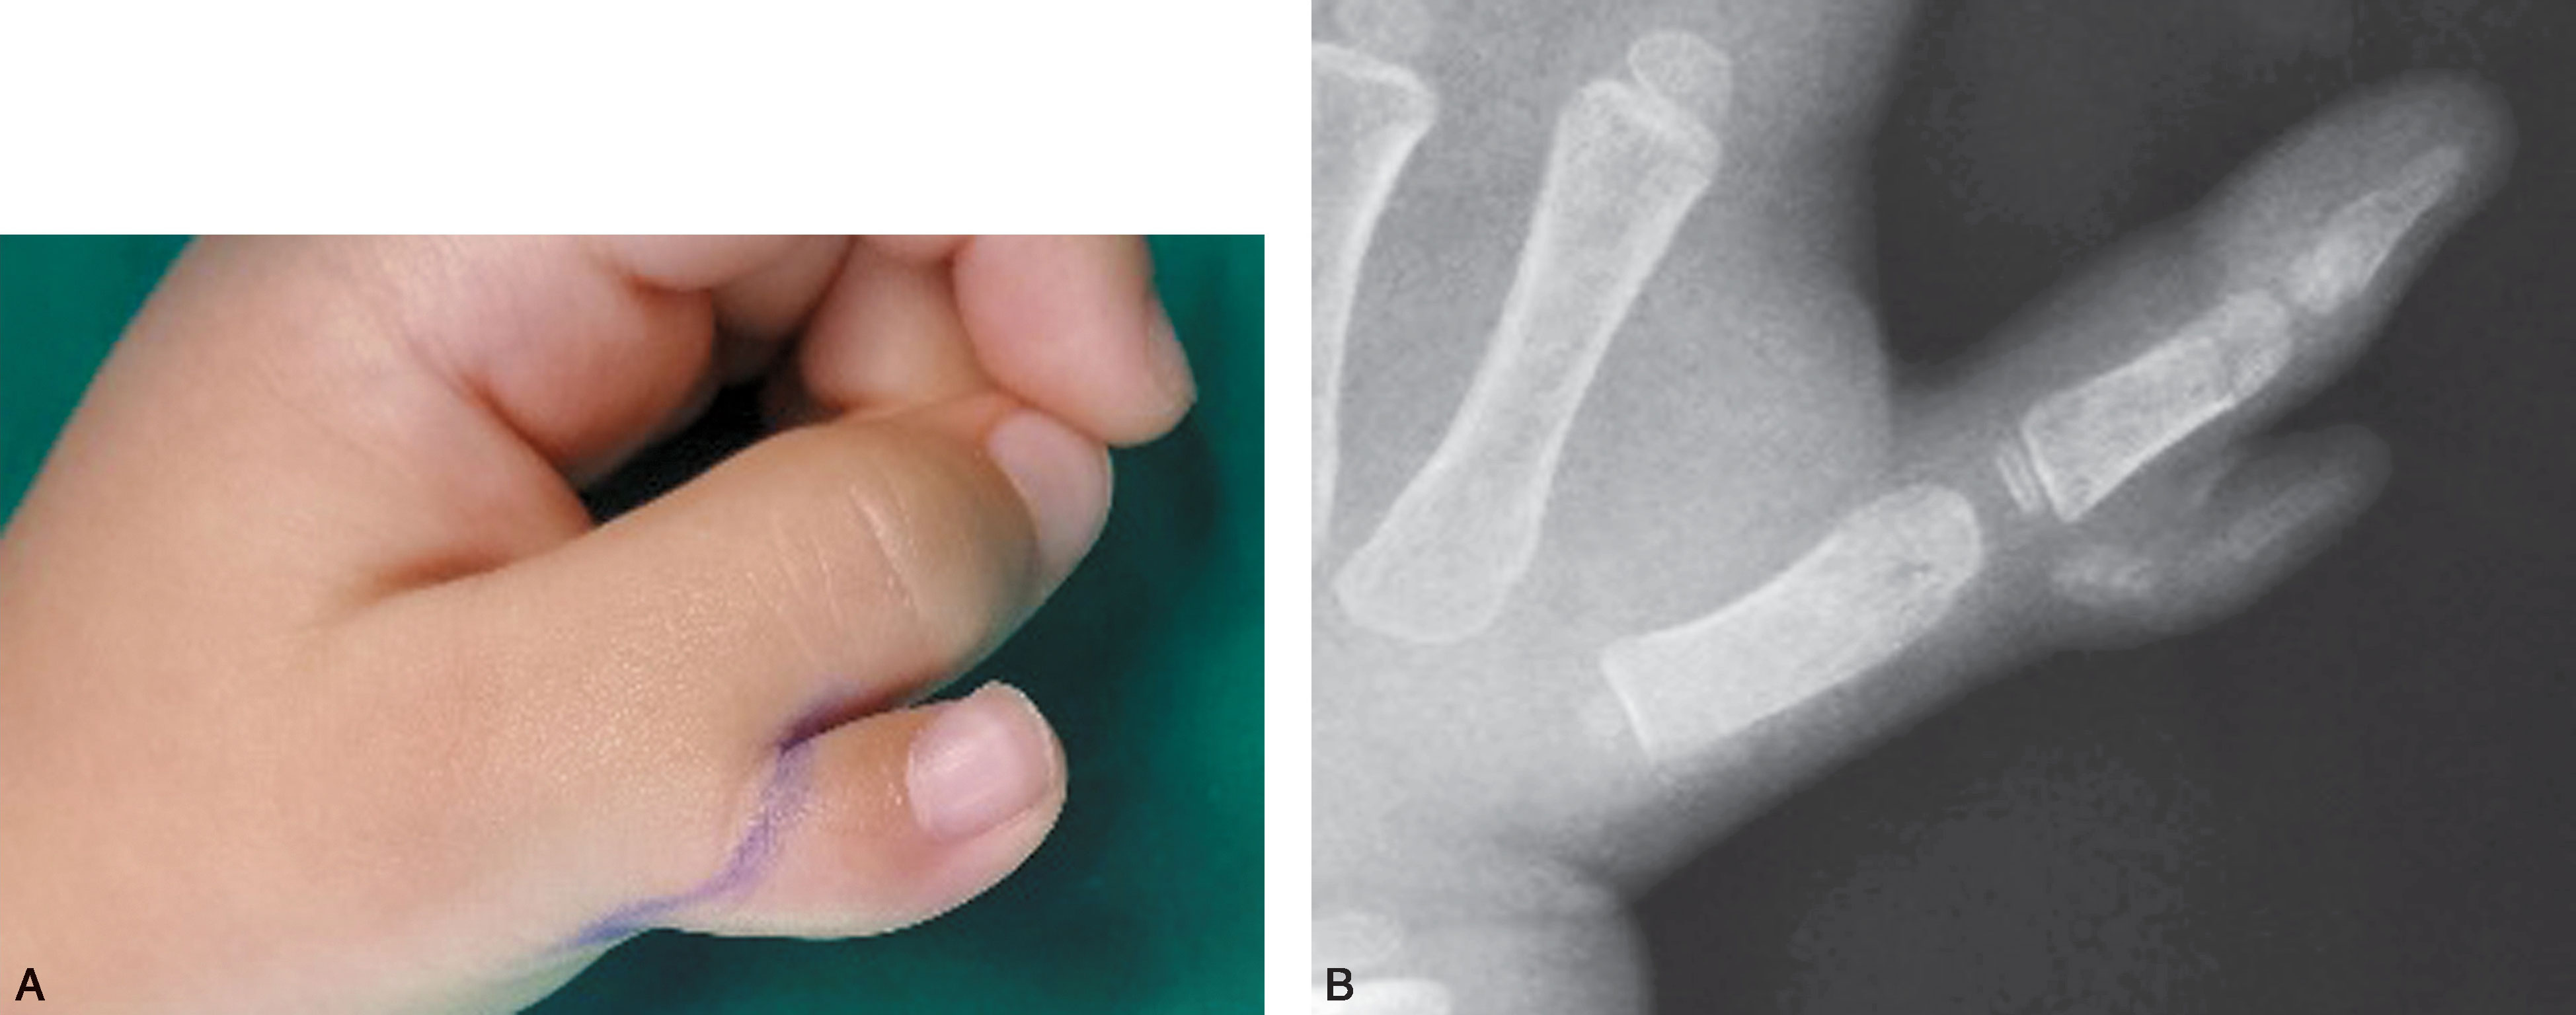

图2-1-3 Ⅰ型病例3

A.体位像显示主、次拇指指甲完全融合在一起,似一个指甲,应选择切除桡侧赘拇,然后需重建甲沟,并尽可能与对侧对称;B.X 线片显示,远节指骨分叉,桡侧部分细小,切除容易,但切除后应注意保持主拇指基底桡侧骨骺板开放。 由于远节指骨基底骨骺为不正常的倒V 形,术后骨骺生长仍可能异常,导致保留下来的远节指骨偏斜,需进一步截骨矫正